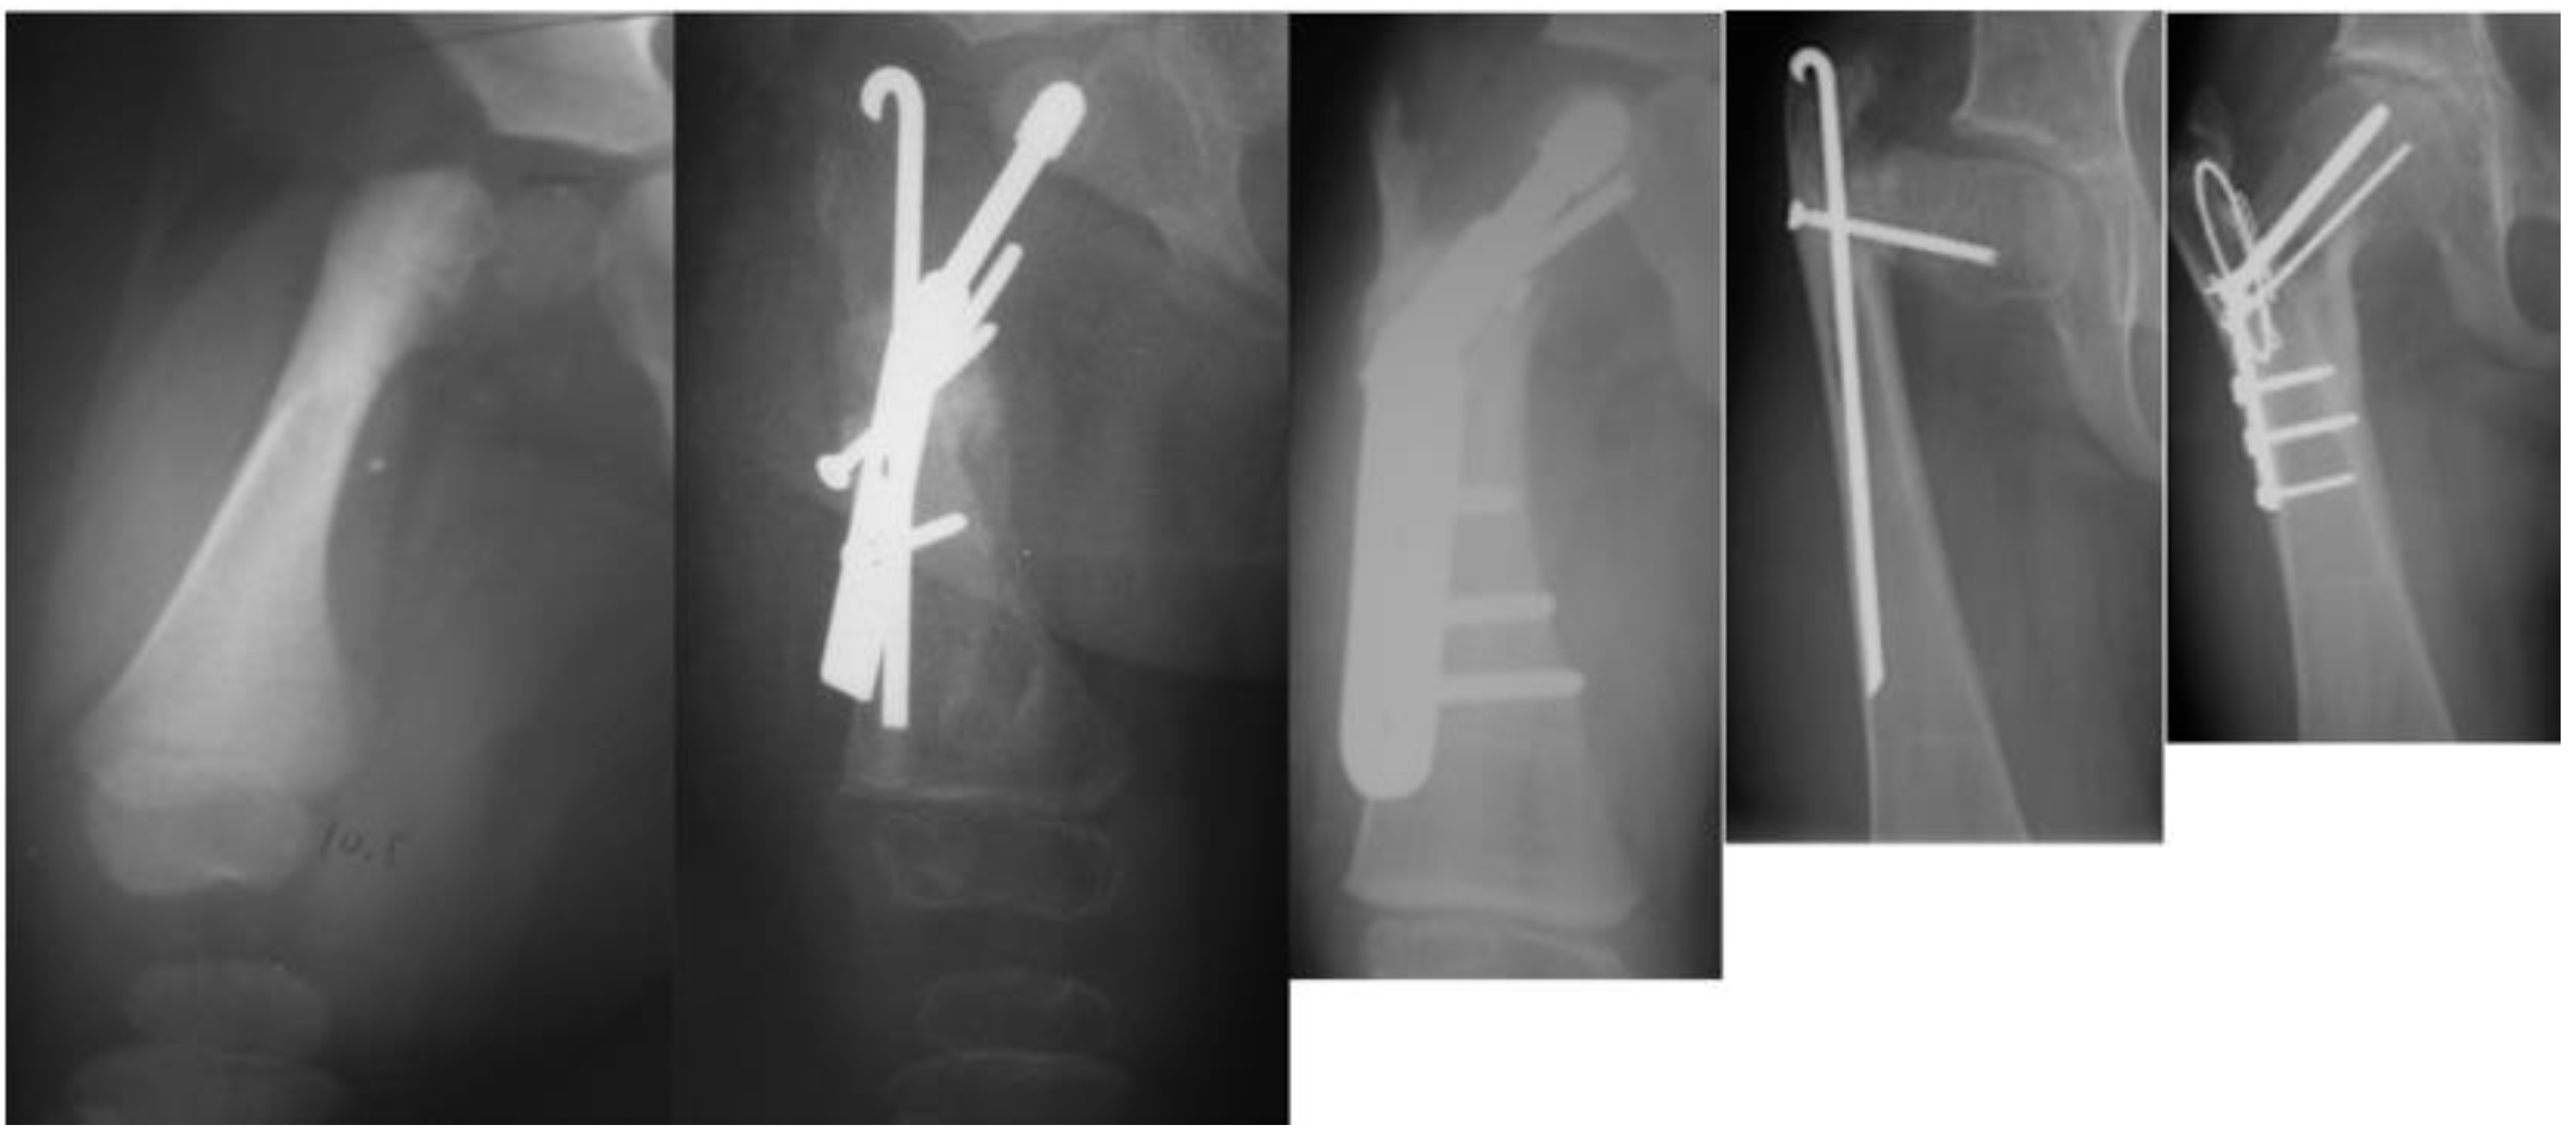

The fixed angle + no BMP2 vs. fixed angle + BMP2 groups were compared (Table 3). There was a significant reduction in persistent delayed ossification in the group treated with BMP2 (p = 0.045), but no significant difference was found in the occurrence of recurrent varus deformity between the two groups (p = 1.00) (Figure 6).

Figure 6. Type 1b CFD preop (left); immediately after SH procedure with fixed angle device and insertion of BMP2 into superior femoral neck (middle); and three months after SH procedure showing ossification of the superior femoral neck in the region of the BMP2 (right).